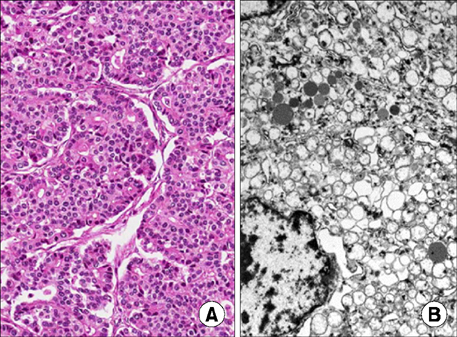

A 9.8×10.0-cm mass of uncertain origin was detected close to the pancreas and spleen on abdominal ultrasonography and abdominal-pelvic CT. The mass was lobulated and heterogeneously enhanced with a multifocal cystic portion around the spleen (

Fig. 1). Fine needle aspiration biopsy (FNAB) was planned and conducted to determine the possibility of neuroendocrine tumor and pancreatoblastoma. However, we could not make a definitive diagnosis; pancreatoblastoma was suspected based on the presence of beta-catenin positive cells. There were no remarkable findings on a preoperative chest CT or a bone scan to detect metastasis.

Fig. 1(A, B) Abdominal-pelvis CT showing a 9.8×10.0-cm, heterogeneous, enhancing, solid, cystic mass in the left upper quadrant.